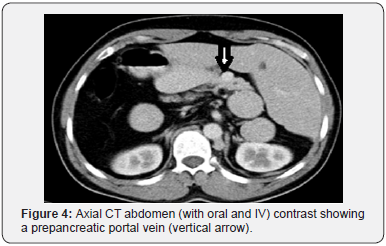

His general investigations (full blood count, random blood glucose, renal and liver profiles) were within normal ranges. His CXR showed normal lungs, levocardia and a right-sided gastric bubble. ECG revealed no abnormalities. A trans-thoracic echocardiography was normal apart from unusual drainage of hepatic veins directly into the right atrium. A multi-detector CT (MDCT) scan of the abdomen (with oral and intravenous contrast) confirmed the hiatus hernia (Figure 1) and revealed a right-sided stomach, a two-humped left-sided liver (Figure 2), polysplenia (three splenic masses, two on the left beneath the liver and one on the right) (Figure 3), a pre-pancreatic portal vein (Figure 4) and an absent inferior vena cava (IVC) with a direct continuation of azygous and hemi-azygous veins (Figure 5). Therefore, CT findings were consistent with heterotaxy syndrome with a left isomerism (polysplenia syndrome).

In a similar report the hepatic veins converged into a virtually thin supra-hepatic IVC draining into the right atrium [9]. Another report described an exceedingly rare occurrence of a left-sided IVC with heterotaxy polysplenia syndrome [17]. Pre-pancreatic or pre-duodenal portal vein (PDPV) is a rare anomaly when the portal vein courses anterior to the pancreas and duodenum, and it is a well-known association with heterotaxy syndrome [3,15-17]. This venous anomalous is usually asymptomatic, however, it could rarely compress the common bile duct causing cholelithiasis which would be an indication for surgical intervention, and on that occasion a precise preoperative evaluation of PDPV anatomy with MDCT is mandatory to avoid any degrees of damage to this anomalous vein [18].